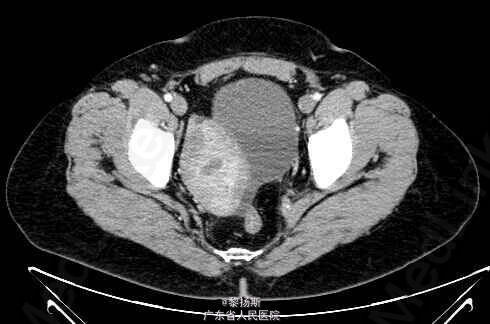

女性,42岁,”发现盆腔包块2年”,无腹痛,无异常阴道流血;自述10年前曾因“盆腔炎” 在外院手术治疗,切除一侧附件,具体不详,有子宫肌瘤病史。

查体:生命体征平稳。腹部可触及包块。影像学:左侧附件区见一囊实性占位,边界清晰,囊性成分较多,增强内可见分隔,囊壁强化明显,并可见强化壁结节。实性成分强化明显。盆腔未见明显肿大淋巴结,未见明显积液。鉴别诊断:卵巢浆液性囊腺癌:也表现为附件囊实性包块,可见分隔,亦可见强化壁结节,鉴别诊断欠困难,有文献称CA125较透明细胞癌升高。病理示:左侧卵巢透明细胞癌。

诊断:左侧卵巢透明细胞癌

原发性卵巢肿瘤分为三种类型,既上皮肿瘤、性索间质肿瘤、生殖细胞肿瘤,卵巢上皮肿瘤依据上皮细胞的类型又分为浆液性癌、粘液性癌、子宫内膜样癌及透明细胞癌。卵巢透明细胞癌是一种起源于苗勒管的卵巢上皮恶性肿瘤,约占卵巢上皮癌的5%,恶性程度高。多发生于成年女性,几乎所有患者诊断时年龄均为25岁以上,临床表现以腹部肿块最常见。透明细胞癌影像上以囊实性肿块多见,并以囊性部分为主,内可见分隔,并可见强化壁结节。实性部分表现为腔内突起,形态不一,乳头或息肉状,部分呈类圆形。肿瘤血供丰富,动脉期明显强化,静脉期及平衡期仍持续强化。难与浆液性囊腺癌鉴别。有文献报导,与浆液性囊腺癌比较,卵巢透明细胞癌具有不同的临床及分子生物学特点:①术前血清CA125值较低,腹腔积液出现几率少,术后残余肿瘤较小。②肿瘤单侧发生,乳头状突起呈分级分支模式。③合并子宫内膜异位症,尽管不特异,也应考虑该肿瘤可能。④免疫组化:Wilms瘤I基因(WT1)和雌激素受体(ER)表达多呈阴性。术前诊断比较困难,确诊主要依靠病理学检查。